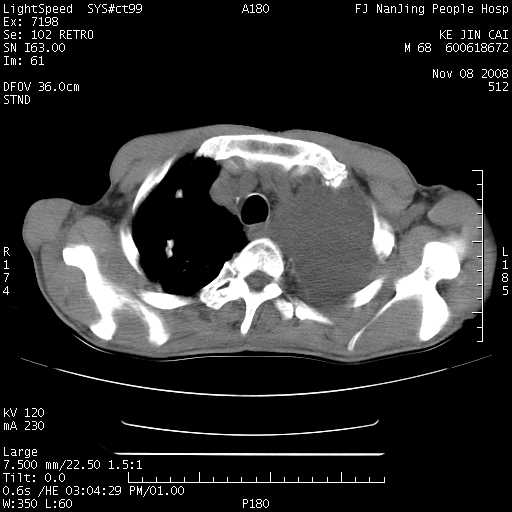

是个很有看头的病例,咋人气那么不旺?没多少人兴趣呢?这个病例几大怪:1   恶性肿瘤侵犯心肌左房怪,心肌一般不会被恶性肿瘤侵犯吧?2   左下肺均匀实变怪,内无含气,有别一般不张实变,含气肺泡完全为液体取代,而非一般不张实变的肺萎陷,冷不丁还以为是肿大的脾脏3   肿瘤本身怪,像tb肺不张4   这么有看头的病例没人气怪。呵呵。

追查病史,咳嗽,患者无发热,血象不高。据说2年前胸片检查怀疑肺ca曾行纤支镜检查,病理未见到癌细胞。无确切资料。

恶性肿瘤,以肺肉瘤可能大。定性诊断穿刺活检还是比较方便的。

左肺恶性肿瘤侵犯肺动脉,左心房内瘤栓,胸膜转移。